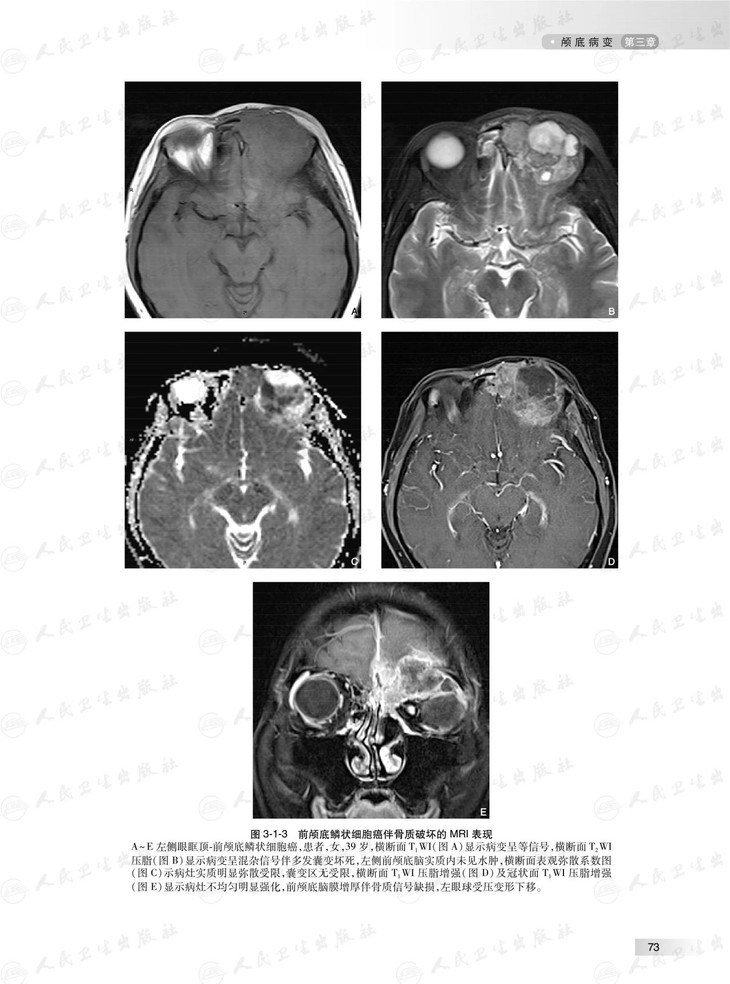

本书根据头颈部影像临床工作场景,对头颈部影像学征象或表现进行系统讲解和分析,头颈部包括的部位多,结构复杂细微,病变种类繁杂,每个部位的影像学征象和表现各有特点,据此,本书按照颅底、耳部、鼻腔与鼻窦、眼球与眼眶、咽喉部、口腔、颌面部、舌骨上颈部间隙和舌骨下颈部间隙等部位各成一章。头颈部外伤性病变有其自身特点,故独立成章。本书图文并茂,具有全面、系统、简洁和清楚的特点。